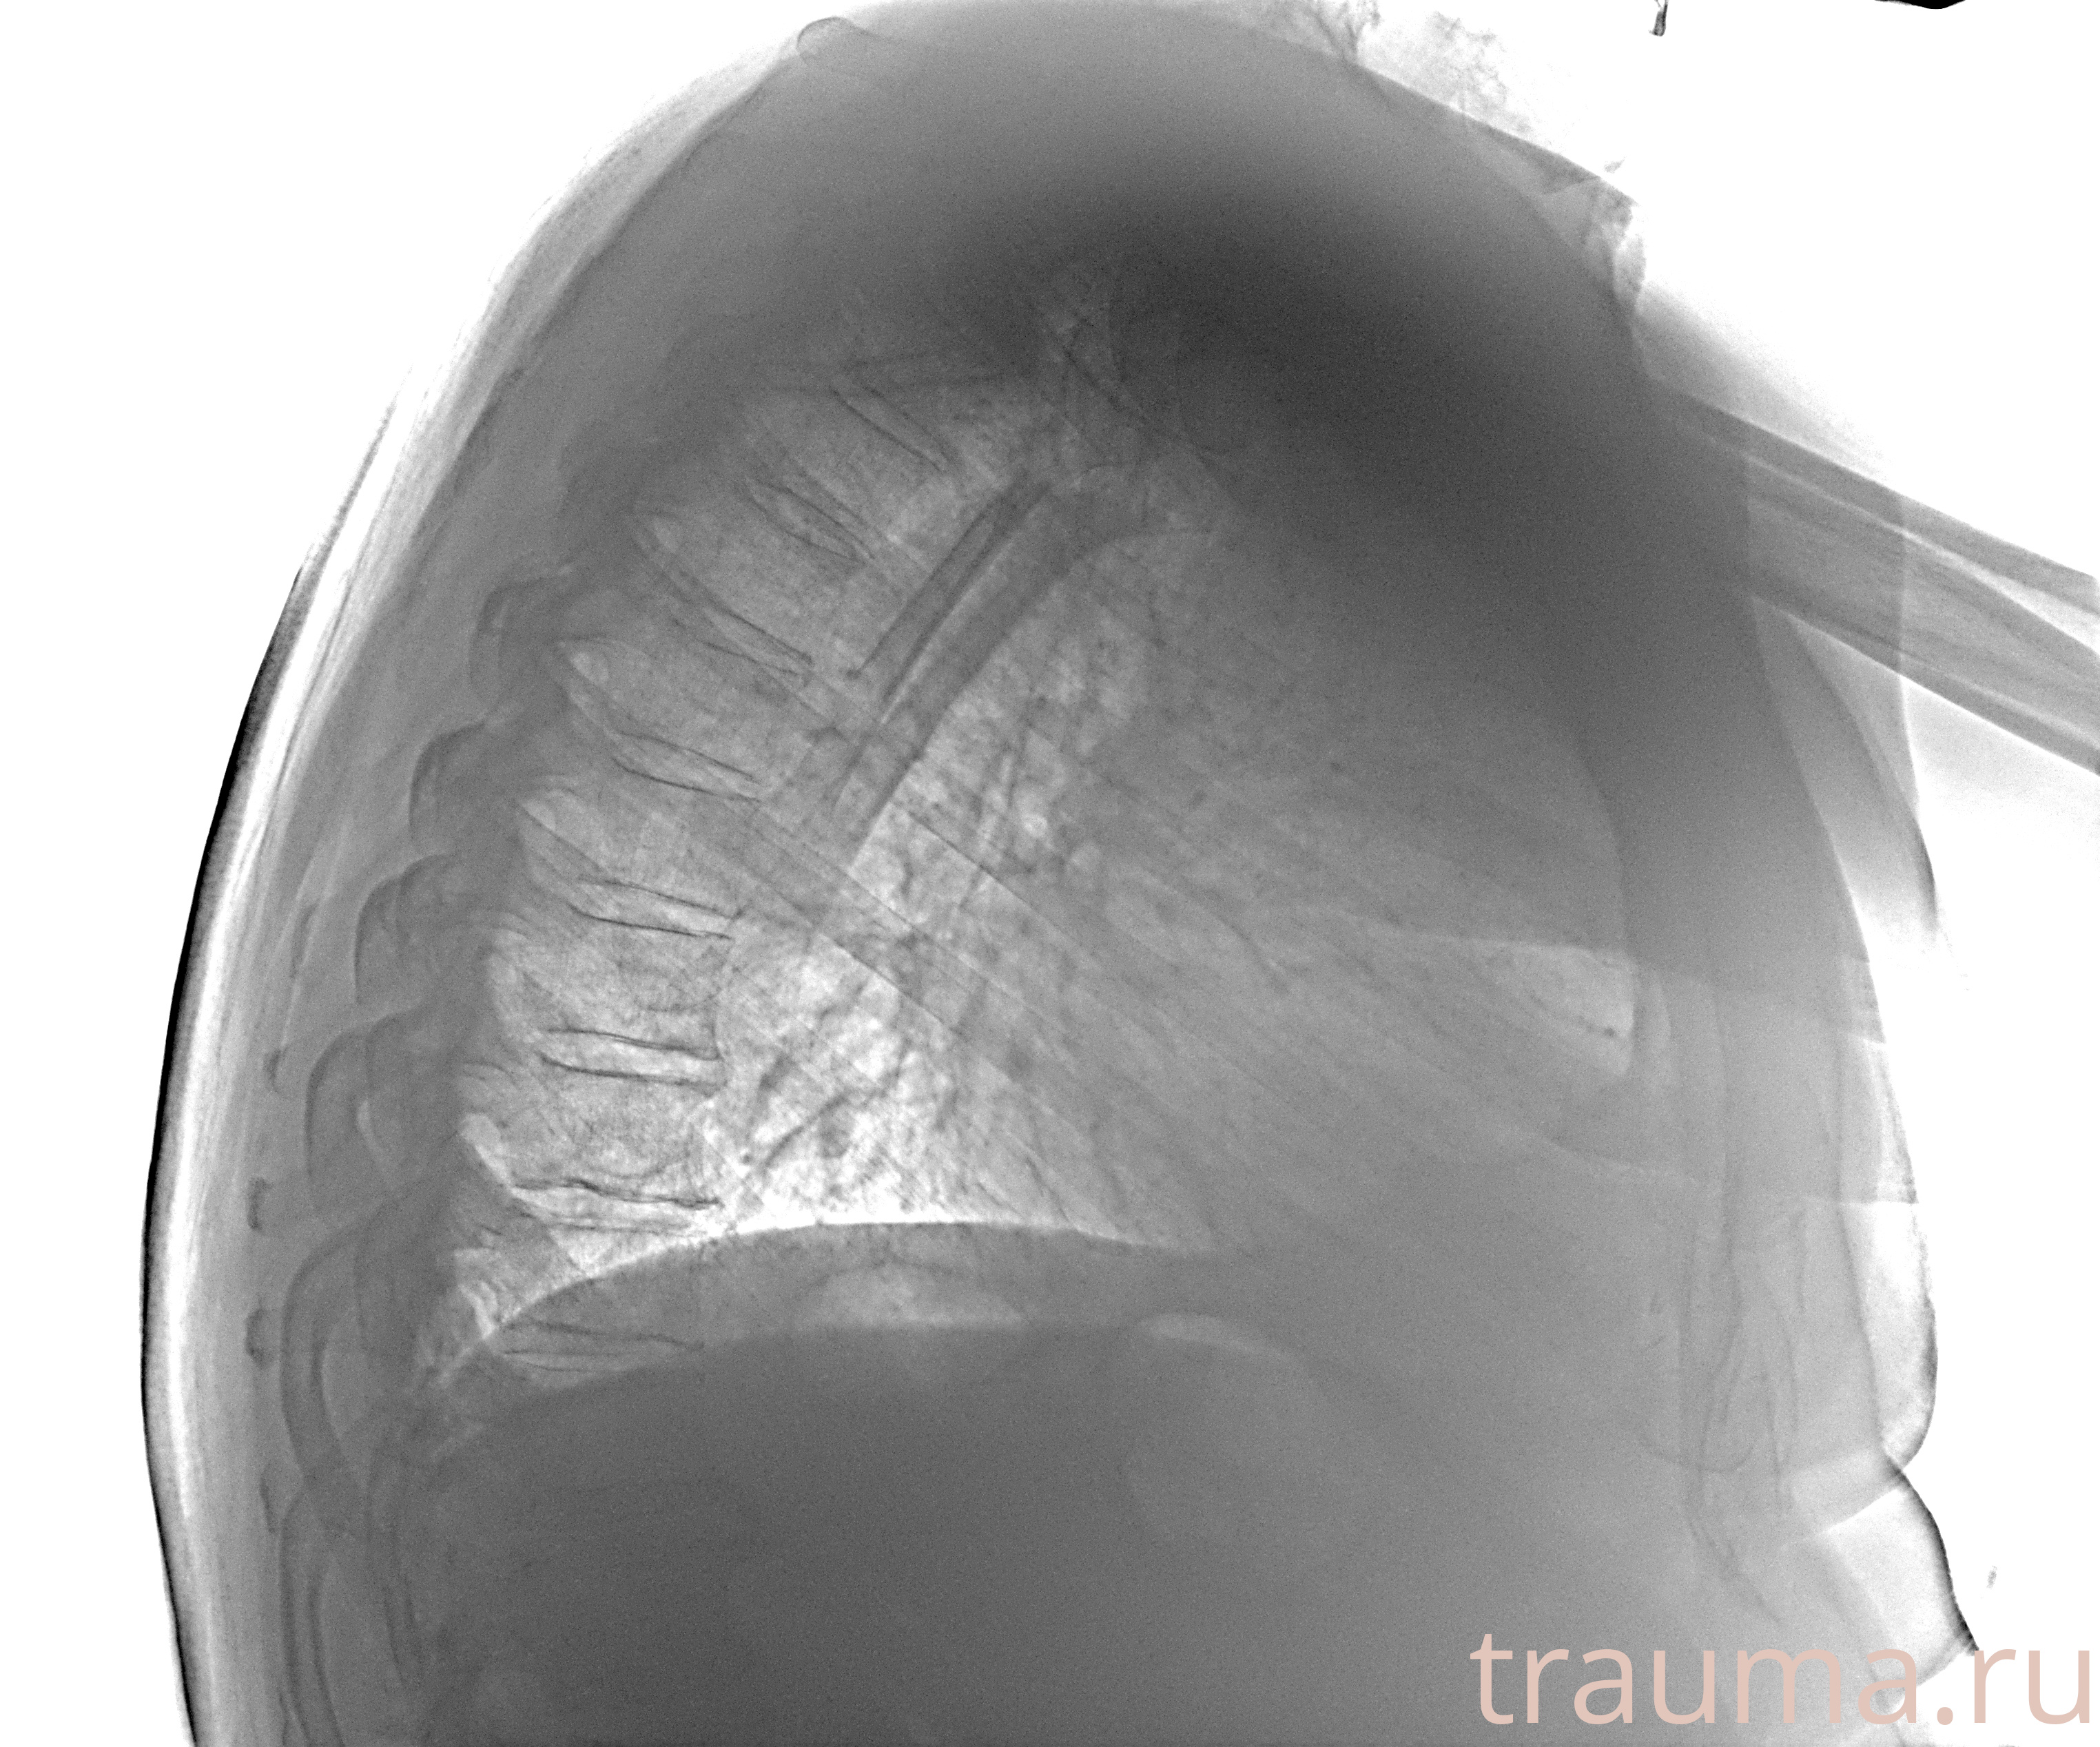

Рентгенограммы

Рентген на дому: по вашему адресу приезжает врач-рентгенолог, травматолог-ортопед с мобильным рентгеновским аппаратом, проводит диагностику травмы или заболевания, делает необходимые рентгенограммы, дает рекомендации по дальнейшему лечению. Получить качественные снимки в домашних условиях возможно благодаря уникальной методике, разработанной МосРентген Центром для института  Склифосовского